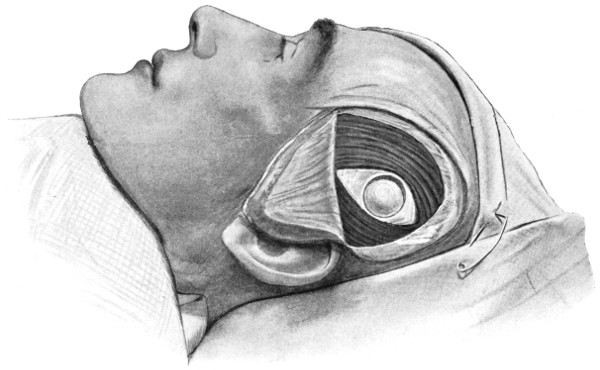

| 45-48. Intermusculo-temporal cerebral decompression | 122, 123 |